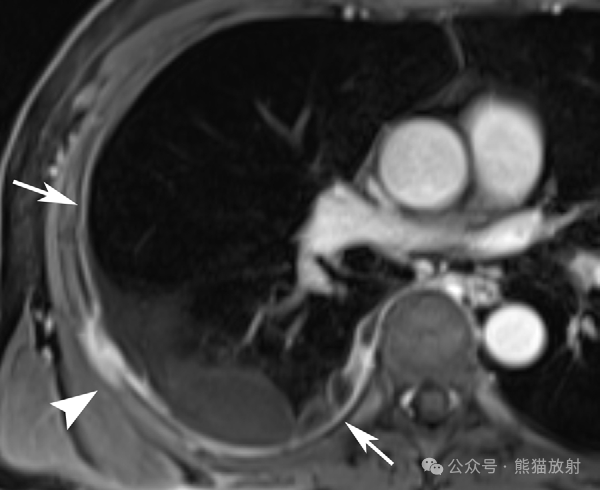

74岁男性,胸膜间皮瘤。胸部轴位T2WI (A) 和对比增强T1WI (B) MR图像显示左侧纵隔胸膜不均匀等高信号肿物,明显不均质强化(箭),沿主动脉周围扩展,左侧胸腔积液(箭头)。